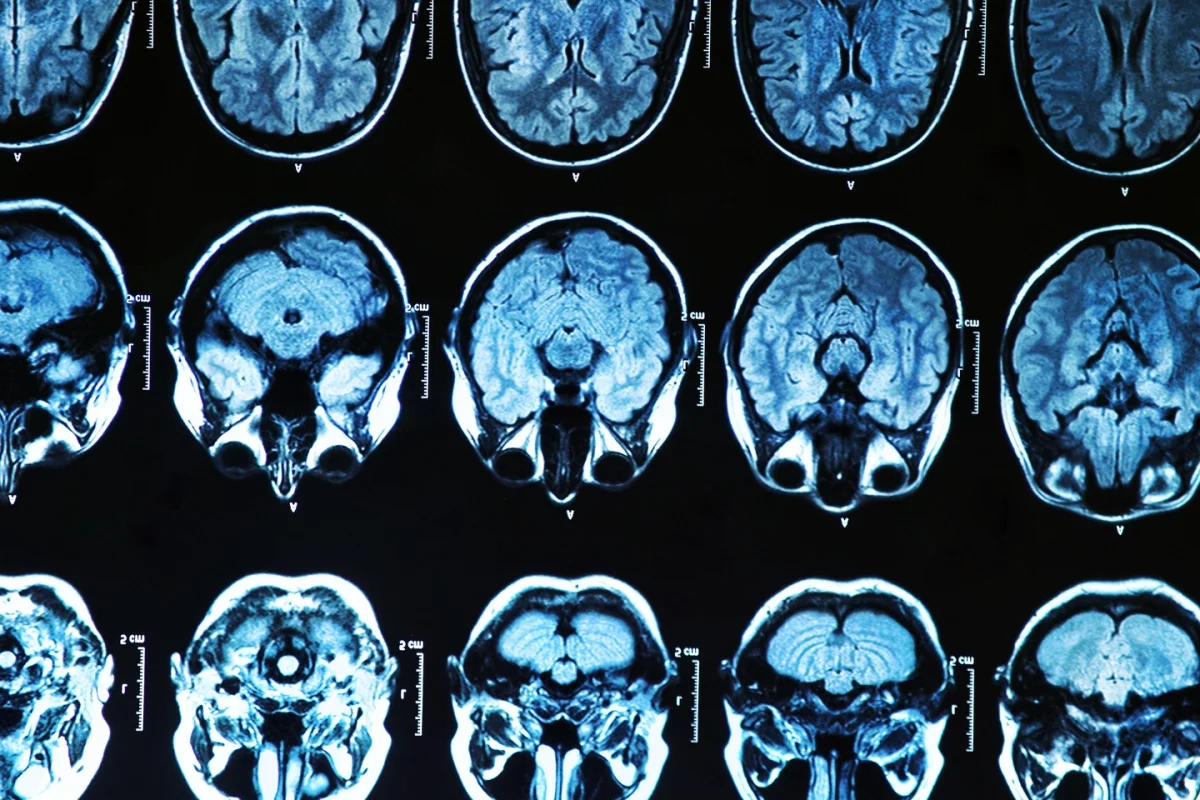

The first human trial examining the safety of a drug designed to reduce the levels of a corrupted protein that is responsible for the devastating effects of Huntington's disease has proven a success. These early, yet exciting results, suggest potential for a new drug that could possibly be adapted to treat other brain disorders such as Alzheimer's and Parkinson's.

Huntington's disease is a devastating neurodegenerative condition caused by a mutation in a gene called huntingtin, which produces a protein of the same name. When this mutation is present the huntingtin protein is corrupted and subsequently damages brain cells, resulting in the disease's progressively irreversible effects on motor and cognitive skills.